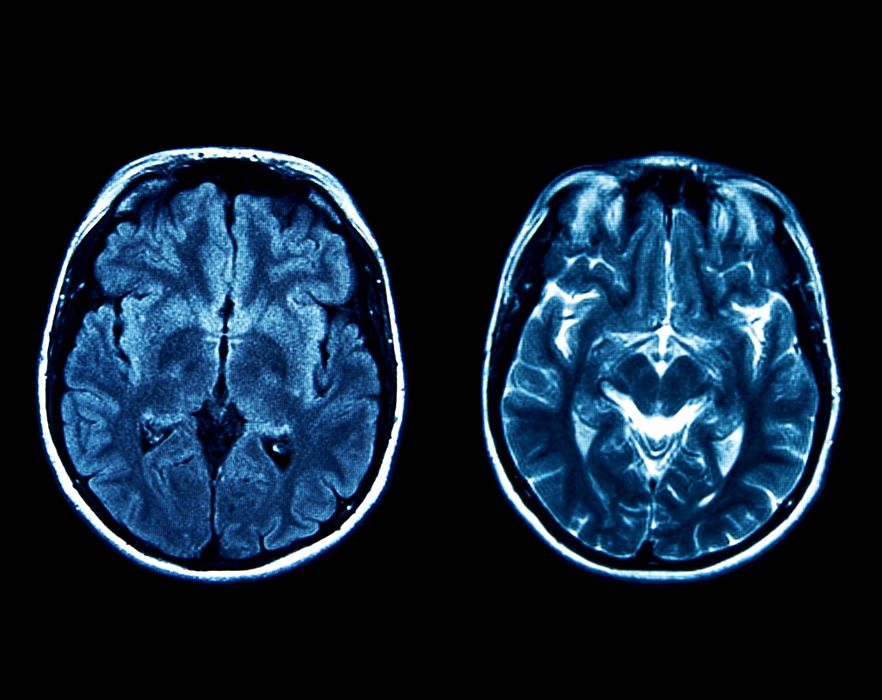

Inteligența Artificială Generativă explică memoria și imaginația umană

Noile progrese în ceea ce privește Inteligența Artificială Generativă ajută la explicarea modului în care amintirile ne permit să învățăm despre lume, să retrăim experiențe vechi și să construim experiențe complet noi pentru imaginație și […]